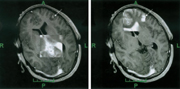

Nachteile der Realzeit-Schichtbilder sind die lange Scannzeit, ca. 2-5 Sekunden, und die vor allem bei

Kernspintomographen mit niedriger Feldstärke (0,2 oder 0,5 Tesla) schlechte Bildqualität. In der

Abbildung ist links ein Realzeit-Schichtbild (0,5 Tesla) und recht ein aus einem präoperativen

3D-Datensatz ermitteltes Bild dargestellt (3D-Sequenz, 0,5 Tesla).

Wichtig ist, dass es sich für den Arzt bezüglich dieser beiden Bildmodalitäten nicht

um eine Entweder-Oder-, sondern vielmehr um eine Sowohl-Als-Auch-Betrachtung handelt. So wird durch das

rechte Bild ein Bezug zur Planung hergestellt, und durch das linke Realzeit-Schichtbild kann die

"Güte" dieser eigentlich "veralteten" Bilddaten beurteilt werden.